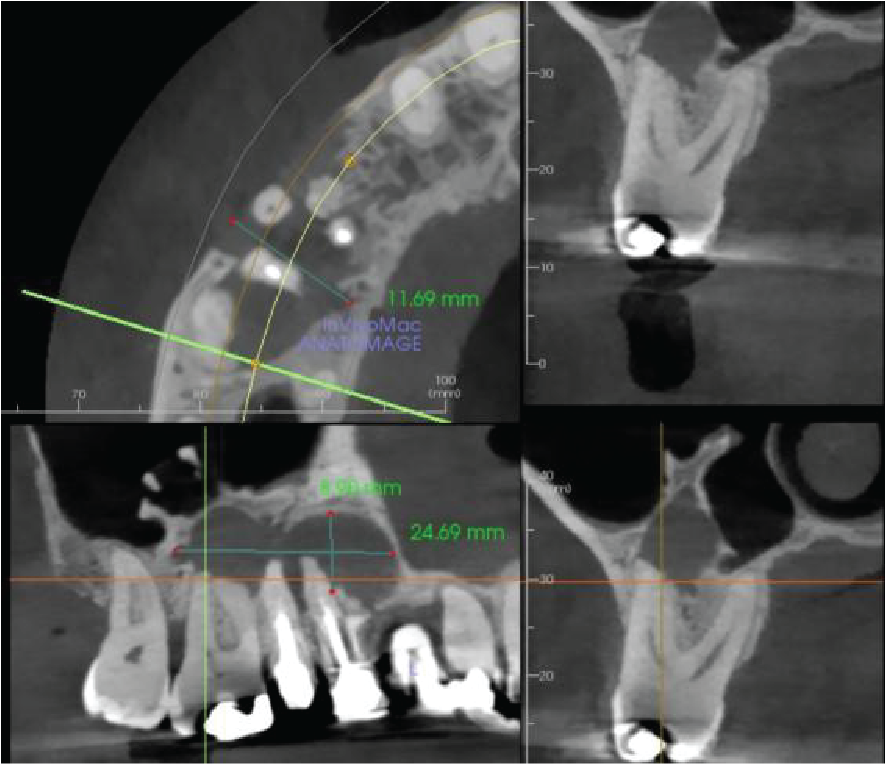

There is apical pathology on the UR6,5,4. The UR6 buccal roots have a large apical radiolucency. The UR4 and UR5 are root treated with large apical radiolucencies and destruction of the buccal cortical plate. These are probably apical granulomas or radicular cysts secondary to chronic apical periodontitis. They are contiguous and measure 12 x 25 x 9 mm.

The right maxillary sinus floor has reactionary bone formation, almost certainly due to the chronic inflammation from the apical disease. However, there is no thickening of the sinus mucosa.

Cropped panoramic and cross section of the alveolar ridge in the UR4-6 region showing chronic apical infection and reactionary bone formation in the right maxillary sinus

Cropped panoramic, axial and cross sections of the alveolar ridge UR4 6 region showing chronic apical infection